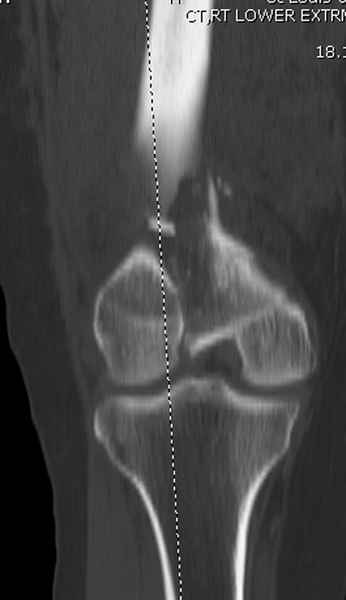

Мы бы не стали открывать, такие переломы срастаются, хотя бы и с краевым дефектом. То есть если удалять стержень потом, то сильно попозже обычного. В приложении пример. Сразу после операции и через 11 мес. Понятное дело, пациент к тому времени давно и не хромал, и функция колена была полная.

При наличии различных имплантов, любые варианты: слева (полу) открытым - мининвазивным, а справа закрытым интрамедуллярным методом, его считаем более чем приемлемым для фиксации данных переломов.

Проксимальная и дистальная блокировка, независимо от техники введения штифта, ретроградно или антеградно, гарантирует сращение сегментарных переломов бедра без укорочения. Штифты диаметром 12 мм с блокировкой сверху и вниз двумя шурупами выдерживают вес 75 кг больного, что позволяет раннюю профилактику контрактур.